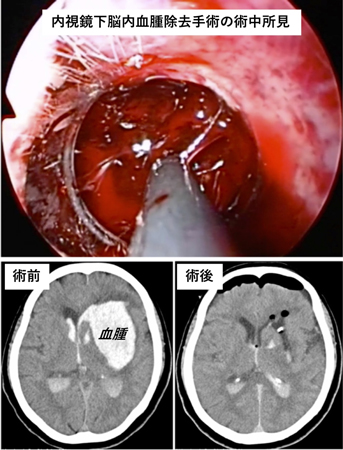

脳内出血に対しては頭部に一ヶ所コインの大きさの穿孔を行い、同部から内視鏡を挿入して血腫を除去する内視鏡下脳内血腫除去術を積極的に行っています。本法により従来の開頭手術に比し短時間かつ低侵襲での血腫除去を行うことができます。低侵襲な手術のため、術後は早期の離床によるリハビリテーションの施行が可能となり、患者さんの予後改善に寄与しています。